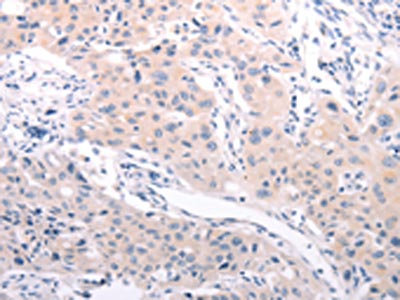

• The image on the left is immunohistochemistry of paraffin-embedded Human cervical cancer tissue using CSB-PA595084(ABCF3 Antibody) at dilution 1/30, on the right is treated with fusion protein. (Original magnification: ×200)

• The image on the left is immunohistochemistry of paraffin-embedded Human lung cancer tissue using CSB-PA595084(ABCF3 Antibody) at dilution 1/30, on the right is treated with fusion protein. (Original magnification: ×200)